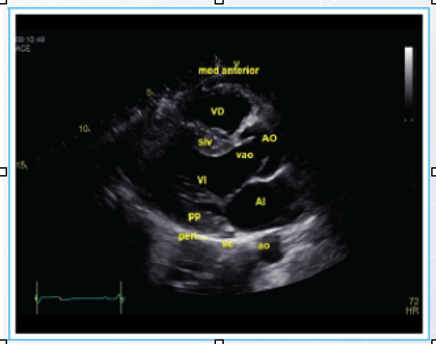

Para obtener una adecuada ventana paraseteral eje largo, buscaremos colocar la sonda en el EIC 3-4 o 4-5 con el indicador del transductor apuntando al hombro derecho del paciente. En esta imagen podremos identificar las siguientes estructuras:

-

Ventrículo derecho

Ventrículo izquierdo

Auricula izquierda

Válvula aórtica

Válvula mitral

Aorta y TSVI

Aorta descendente

Pericardio

La localización del ventrículo izquierdo en el eje paraesternal largo es en el lado izquierdo.